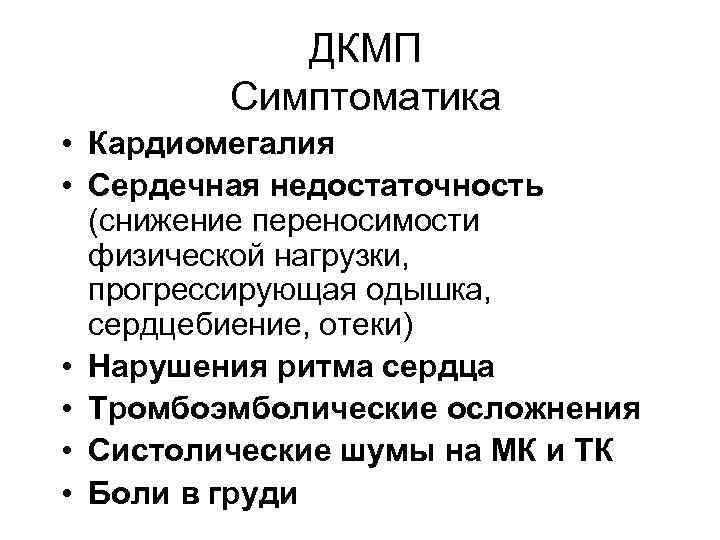

ДКМП Симптоматика • Кардиомегалия • Сердечная недостаточность (снижение переносимости физической нагрузки, прогрессирующая одышка, сердцебиение, отеки) • Нарушения ритма сердца • Тромбоэмболические осложнения • Систолические шумы на МК и ТК • Боли в груди

ДКМП Симптоматика • Кардиомегалия • Сердечная недостаточность (снижение переносимости физической нагрузки, прогрессирующая одышка, сердцебиение, отеки) • Нарушения ритма сердца • Тромбоэмболические осложнения • Систолические шумы на МК и ТК • Боли в груди